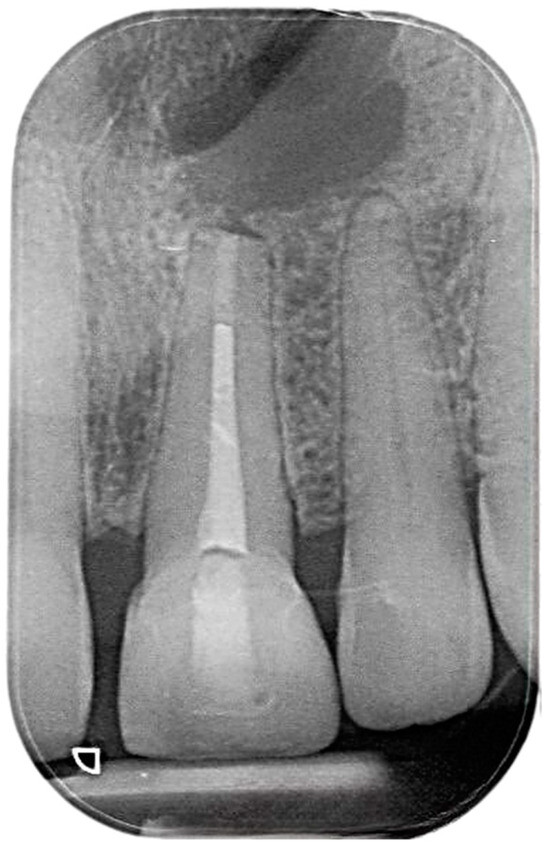

2. Case Presentation

2.2. Delivery of Treatment

2.4. Healing of the Defect and Follow Up